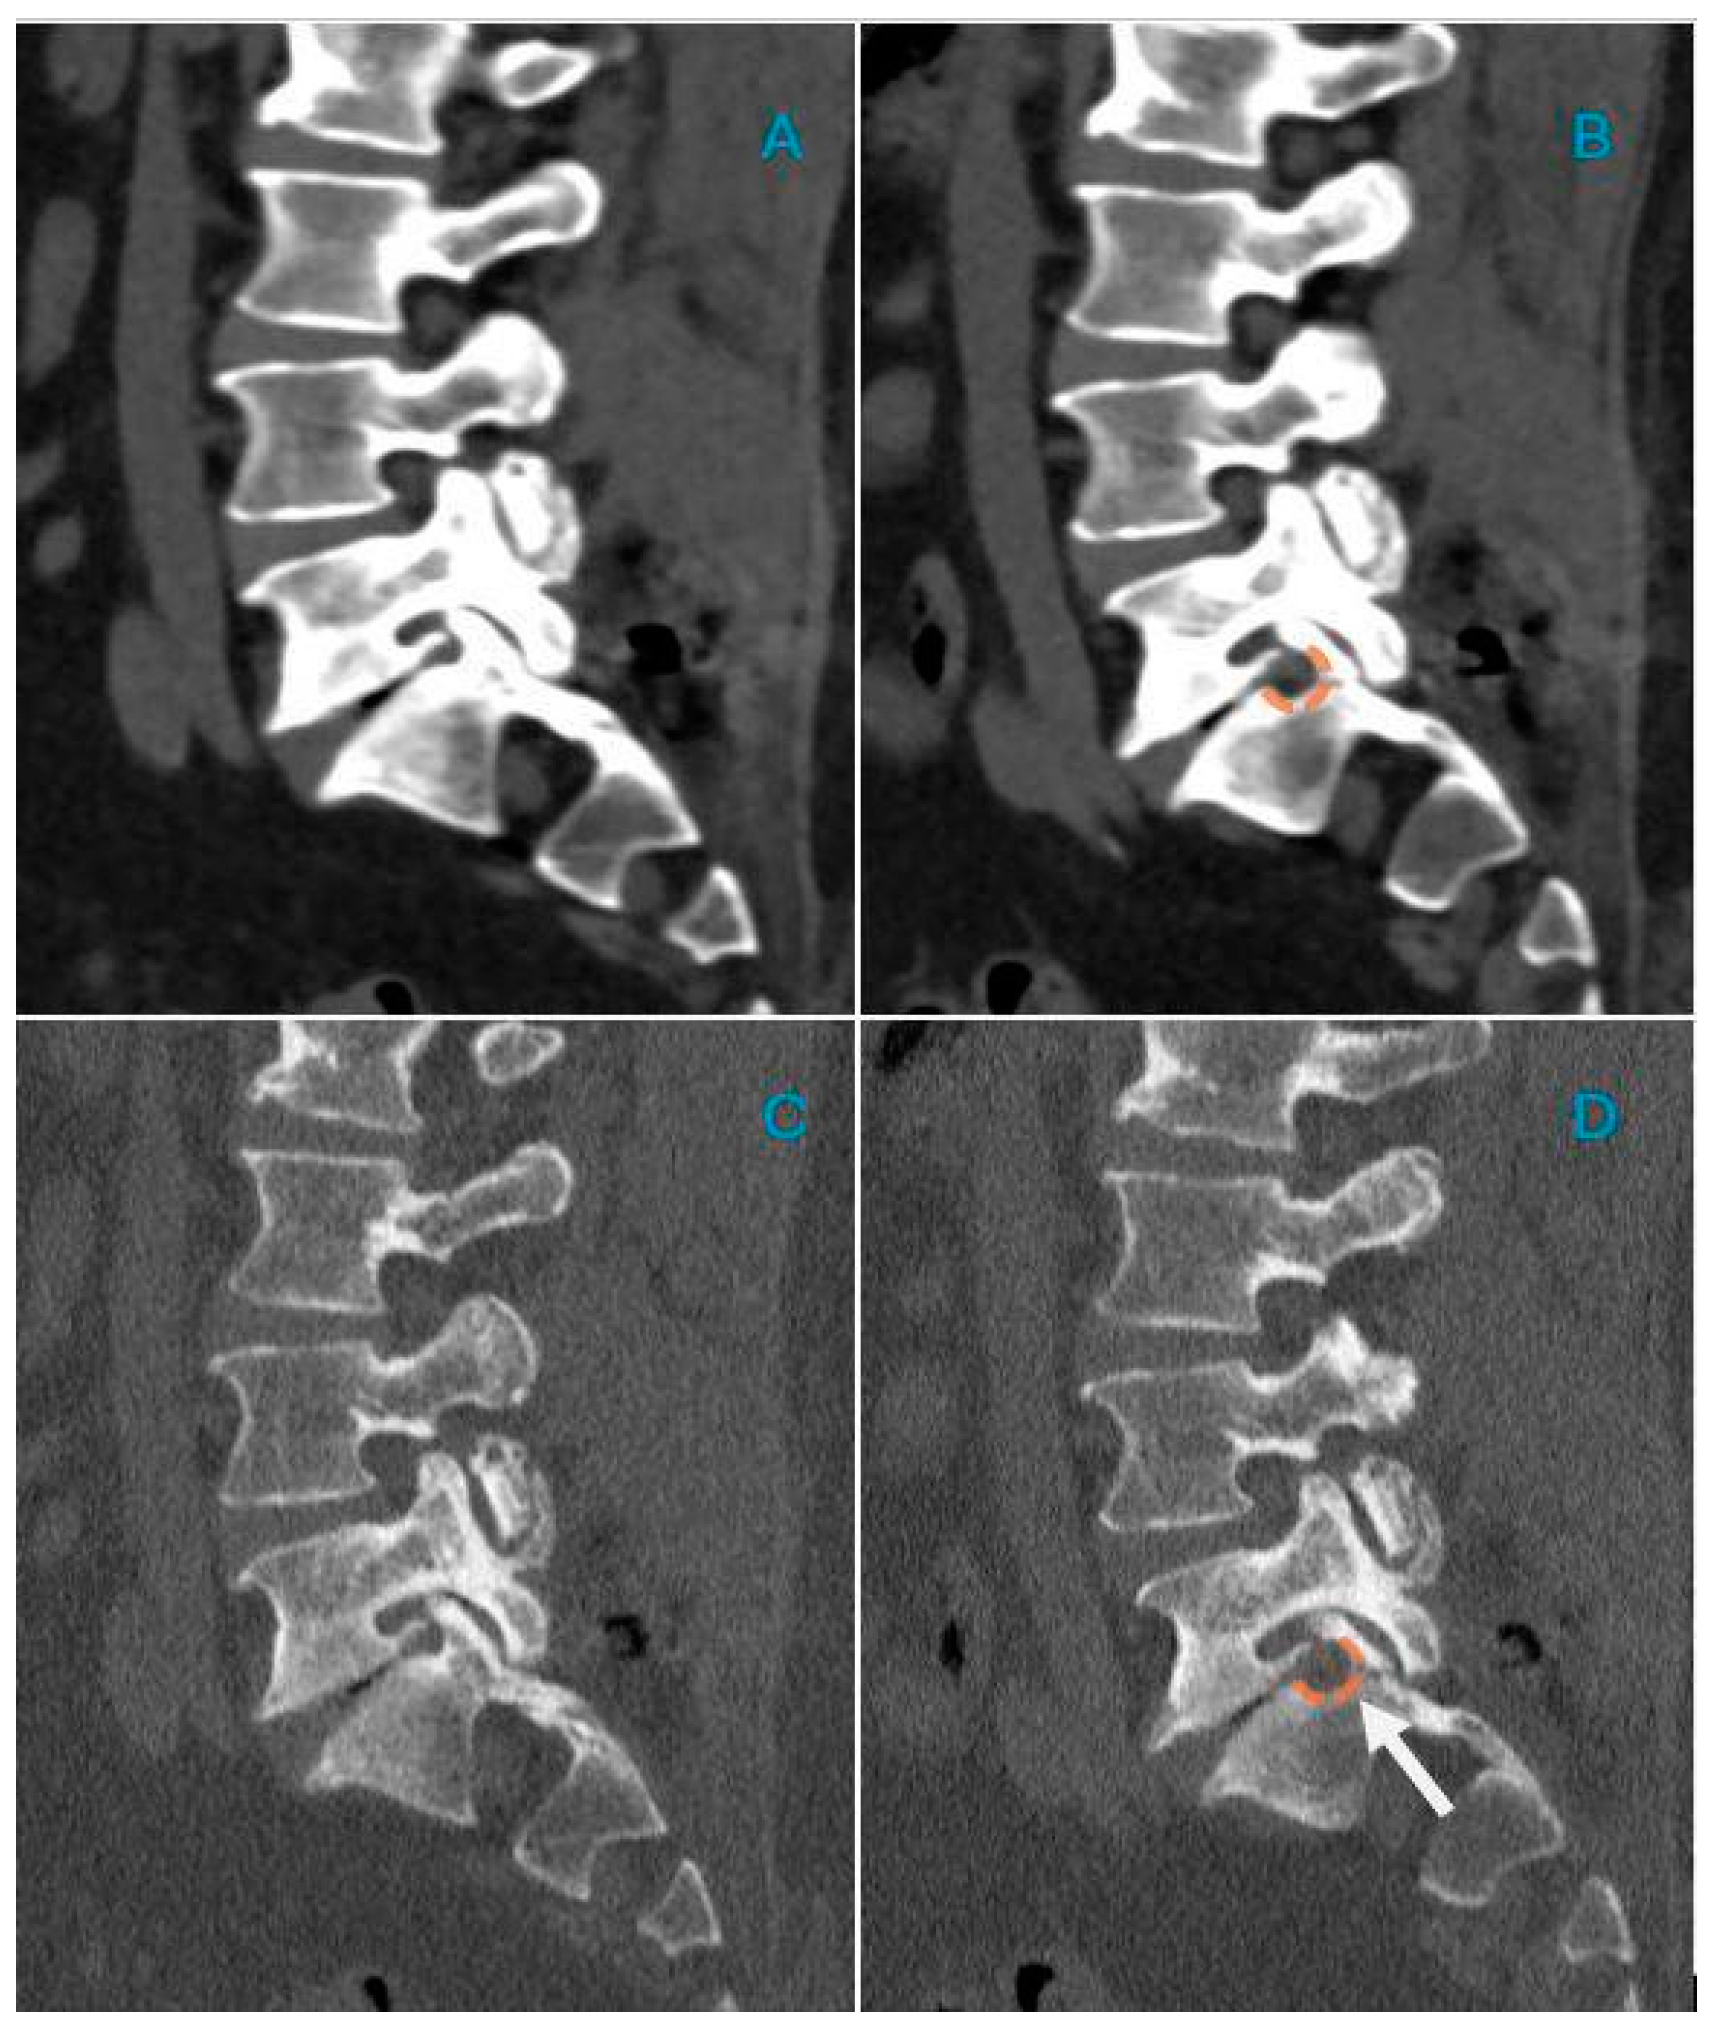

2.4. CT Post-Processing

2.5. Image Analysis